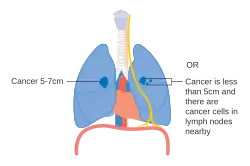

De stadiëring van niet-kleincellige longkanker (NSCLC) vindt in eerste instantie plaats aan de hand van de TNM-classificatie 8ste editie. Deze is gebaseerd op de grootte van de primaire tumor, verspreiding naar lymfeknopen (nodes) en metastasen (uitzaaiingen). Vervolgens wordt op basis van de TNM-parameters de kanker in een groep ingedeeld, die kan variëren van "occulte kanker" (kanker waar de primaire tumor nog niet gevonden is) tot de stadia 0, IA, IB, IIA, IIB, IIIA, IIIB en IV. Deze indeling in een stadiumgroep helpt bij de keuze van behandeling en het inschatten van de prognose.[43] Kleincellig longkanker (SCLC) wordt vanouds geclassificeerd als 'beperkt stadium' (beperkt tot één helft van de borst en binnen het bereik van één enkel verdraagbaar radiotherapieveld) of 'uitgebreide stadium' (verspreide ziekte).[2] De TNM-classificatie en -groepsindeling zijn echter nuttig bij het inschatten van de prognose.[43]

- Schema van belangrijkste kenmerken van longkanker stadiëring

Stadium IIB longkanker -

Een mogelijkheid voor stadium IIB-longkanker, T2b. Indien de tumor zich op 2 cm of minder van de carina bevindt, is het een stadium III -